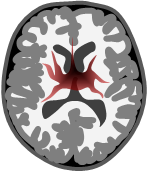

Fjärilsgliom

- Växer centralt i båda hemisfärer

- Engagerar corpus callosum

- Ej botbart.